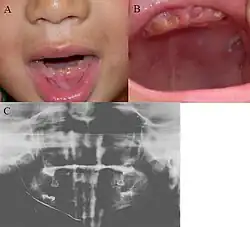

![]() Pacjent z dentinogenesis imperfecta; widać brązowawe zęby z niemal zupełnie startą warstwą szkliwa. Na dole pantomogram u tego samego pacjenta[2] | |

Dentinogenesis imperfecta (ang. dentinogenesis imperfecta, DI) – grupa uwarunkowanych genetycznie zaburzeń rozwoju zębów. Zęby w dentinogenesis imperfecta są przebarwione (najczęściej niebieskoszare albo żółtobrązowe) i przezroczyste. Tkanka zębów jest też nieprawidłowo miękka, co czyni zęby podatnymi na uszkodzenia. Wyróżniono trzy główne typy choroby[3], z których postaci należące do typu I współistnieją z osteogenesis imperfecta.